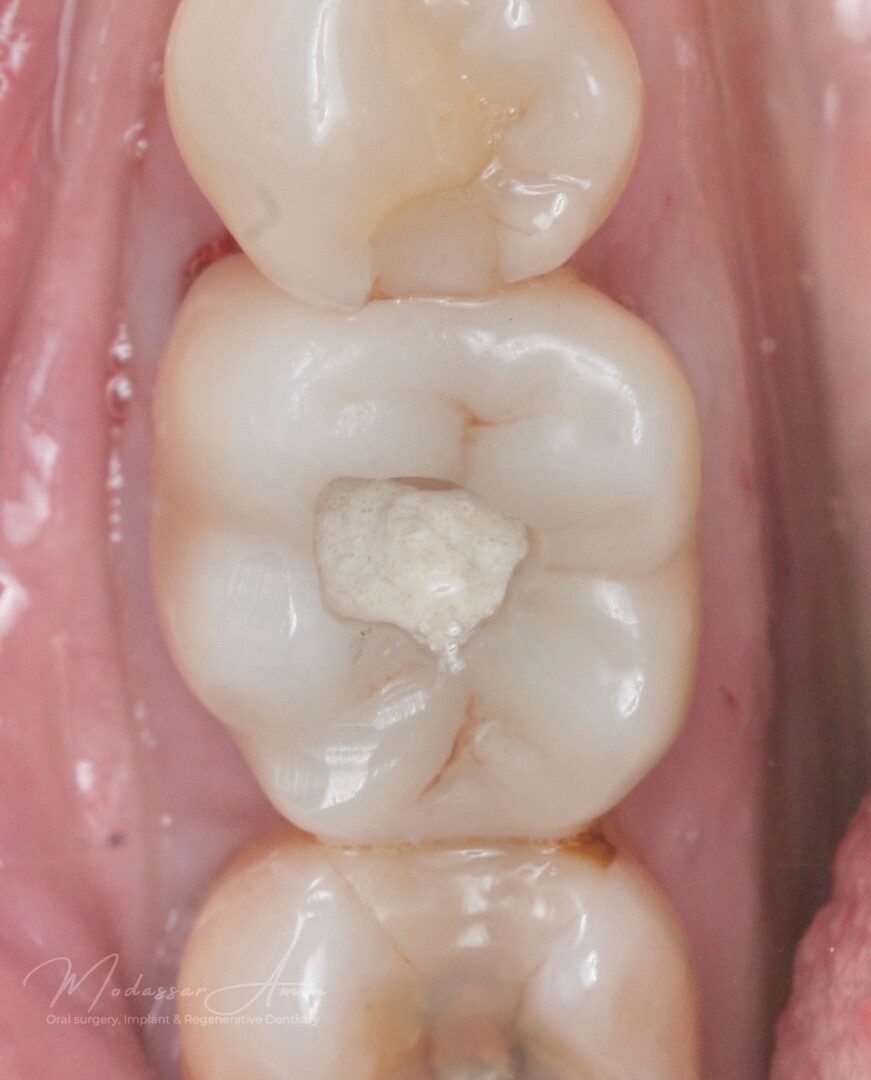

Pasienten presenterte med tann 46 som ikke kunne bevares grunnet en dyptgående infraksjon inn i furkasjonen. Forholdene lå til rette for en immediate implantatbehandling. Ved hjelp av Versah osseodensifikasjonsbor ble det interradikulære beinet ekspandert på en skånsom og forutsigbar måte, noe som ga høy primærstabilitet (>40 Ncm) til tross for en lokal bendefekt apikalt mesialt etter kronisk apikal periodontitt. Den gode stabiliteten muliggjorde bruk av SSA (Sealing Socket Abutment) for forsegling. På grunn av tynn bløtvevsfenotype bukkalt ble behandlingen supplert med bindevevstransplantat (CTG):

Initial